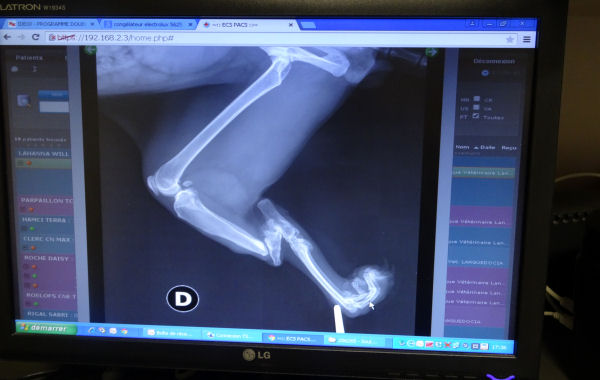

Une fois à la clinique, le véto l’a donc observé et très vite, nous a dit que sa patte serait impossible à récupérer, même si on lui posait cash 10000 euros sur la table, a-t-il précisé. Seule solution, l’amputer, ce qui le soulagera de la douleur permanente que doit lui générer ses os fracturés et les dommages irréversibles sur ses tendons et ses muscles, sans parler de risques élevés d’infection, un bout d’os ayant tendance à créer une plaie à travers la peau. La radio, très impressionnante, n’a fait que confirmer le diagnostic.